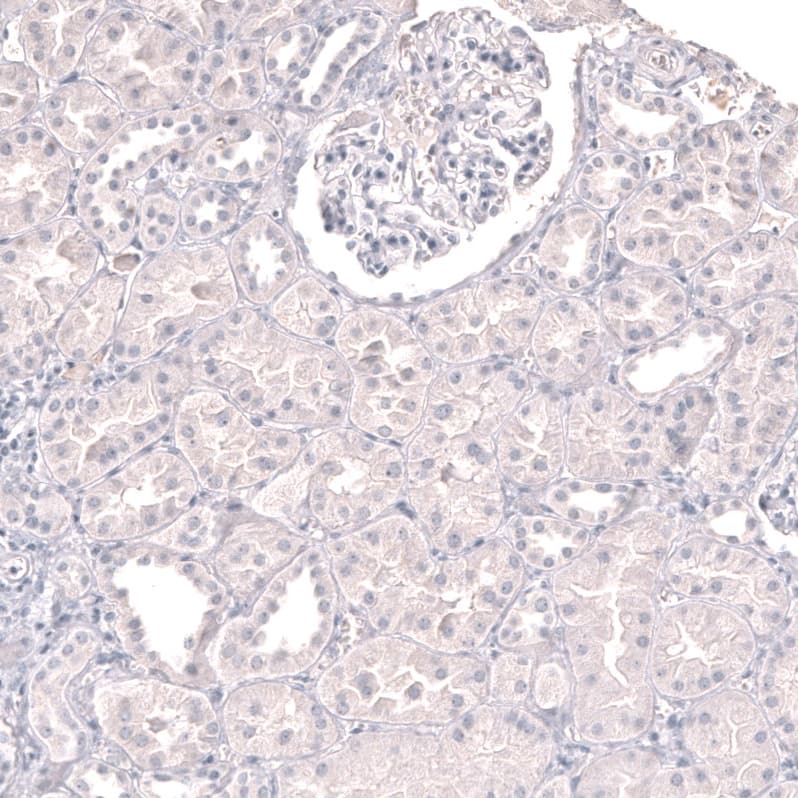

Staining of human kidney shows no positivity in cells in tubules and glomerulus as expected.